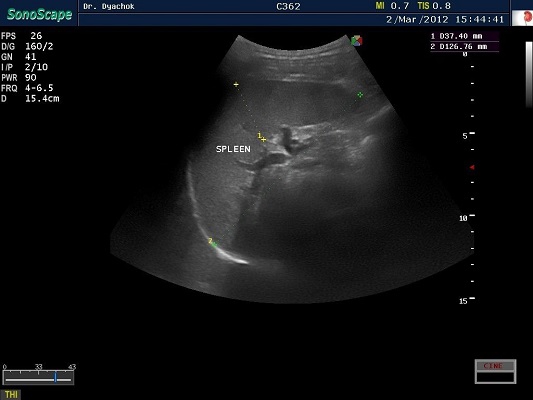

SonoScape S2N Vet – уникальная узи-система, выполненная в виде портативного ноутбука для легкой переноски. Отличается эта система цветным форматом визуализации, а также крайне чувствительными доплеровскими режимами, работающими на уровне премиальных аппаратов. При оптимальной цене – это очень хорошее и сбалансированное решение для ветеринарной клиники.

Диагональ монитора составляет 15,6 дюймов, что обеспечит комфортную работу для врачей и полный спектр визуализации для пациентов. Компактный вес не превышает 5 кг. (вместе с батареей), что оценят выездные бригады скорой помощи или ветеринары, выезжающие на дом.

Цифровая рабочая станция S2N Vet предполагает наличие жесткого диска для записи данных, составление и экспорт отчетов с возможностью добавления изображений, ведение базы данных пациентов.

Данный аппарат является незаменимым помощником в диагностической медицине. Ему нет конкурентов по оснащению, компактности и цене, а значит пора сделать правильный выбор для вашей клиники.